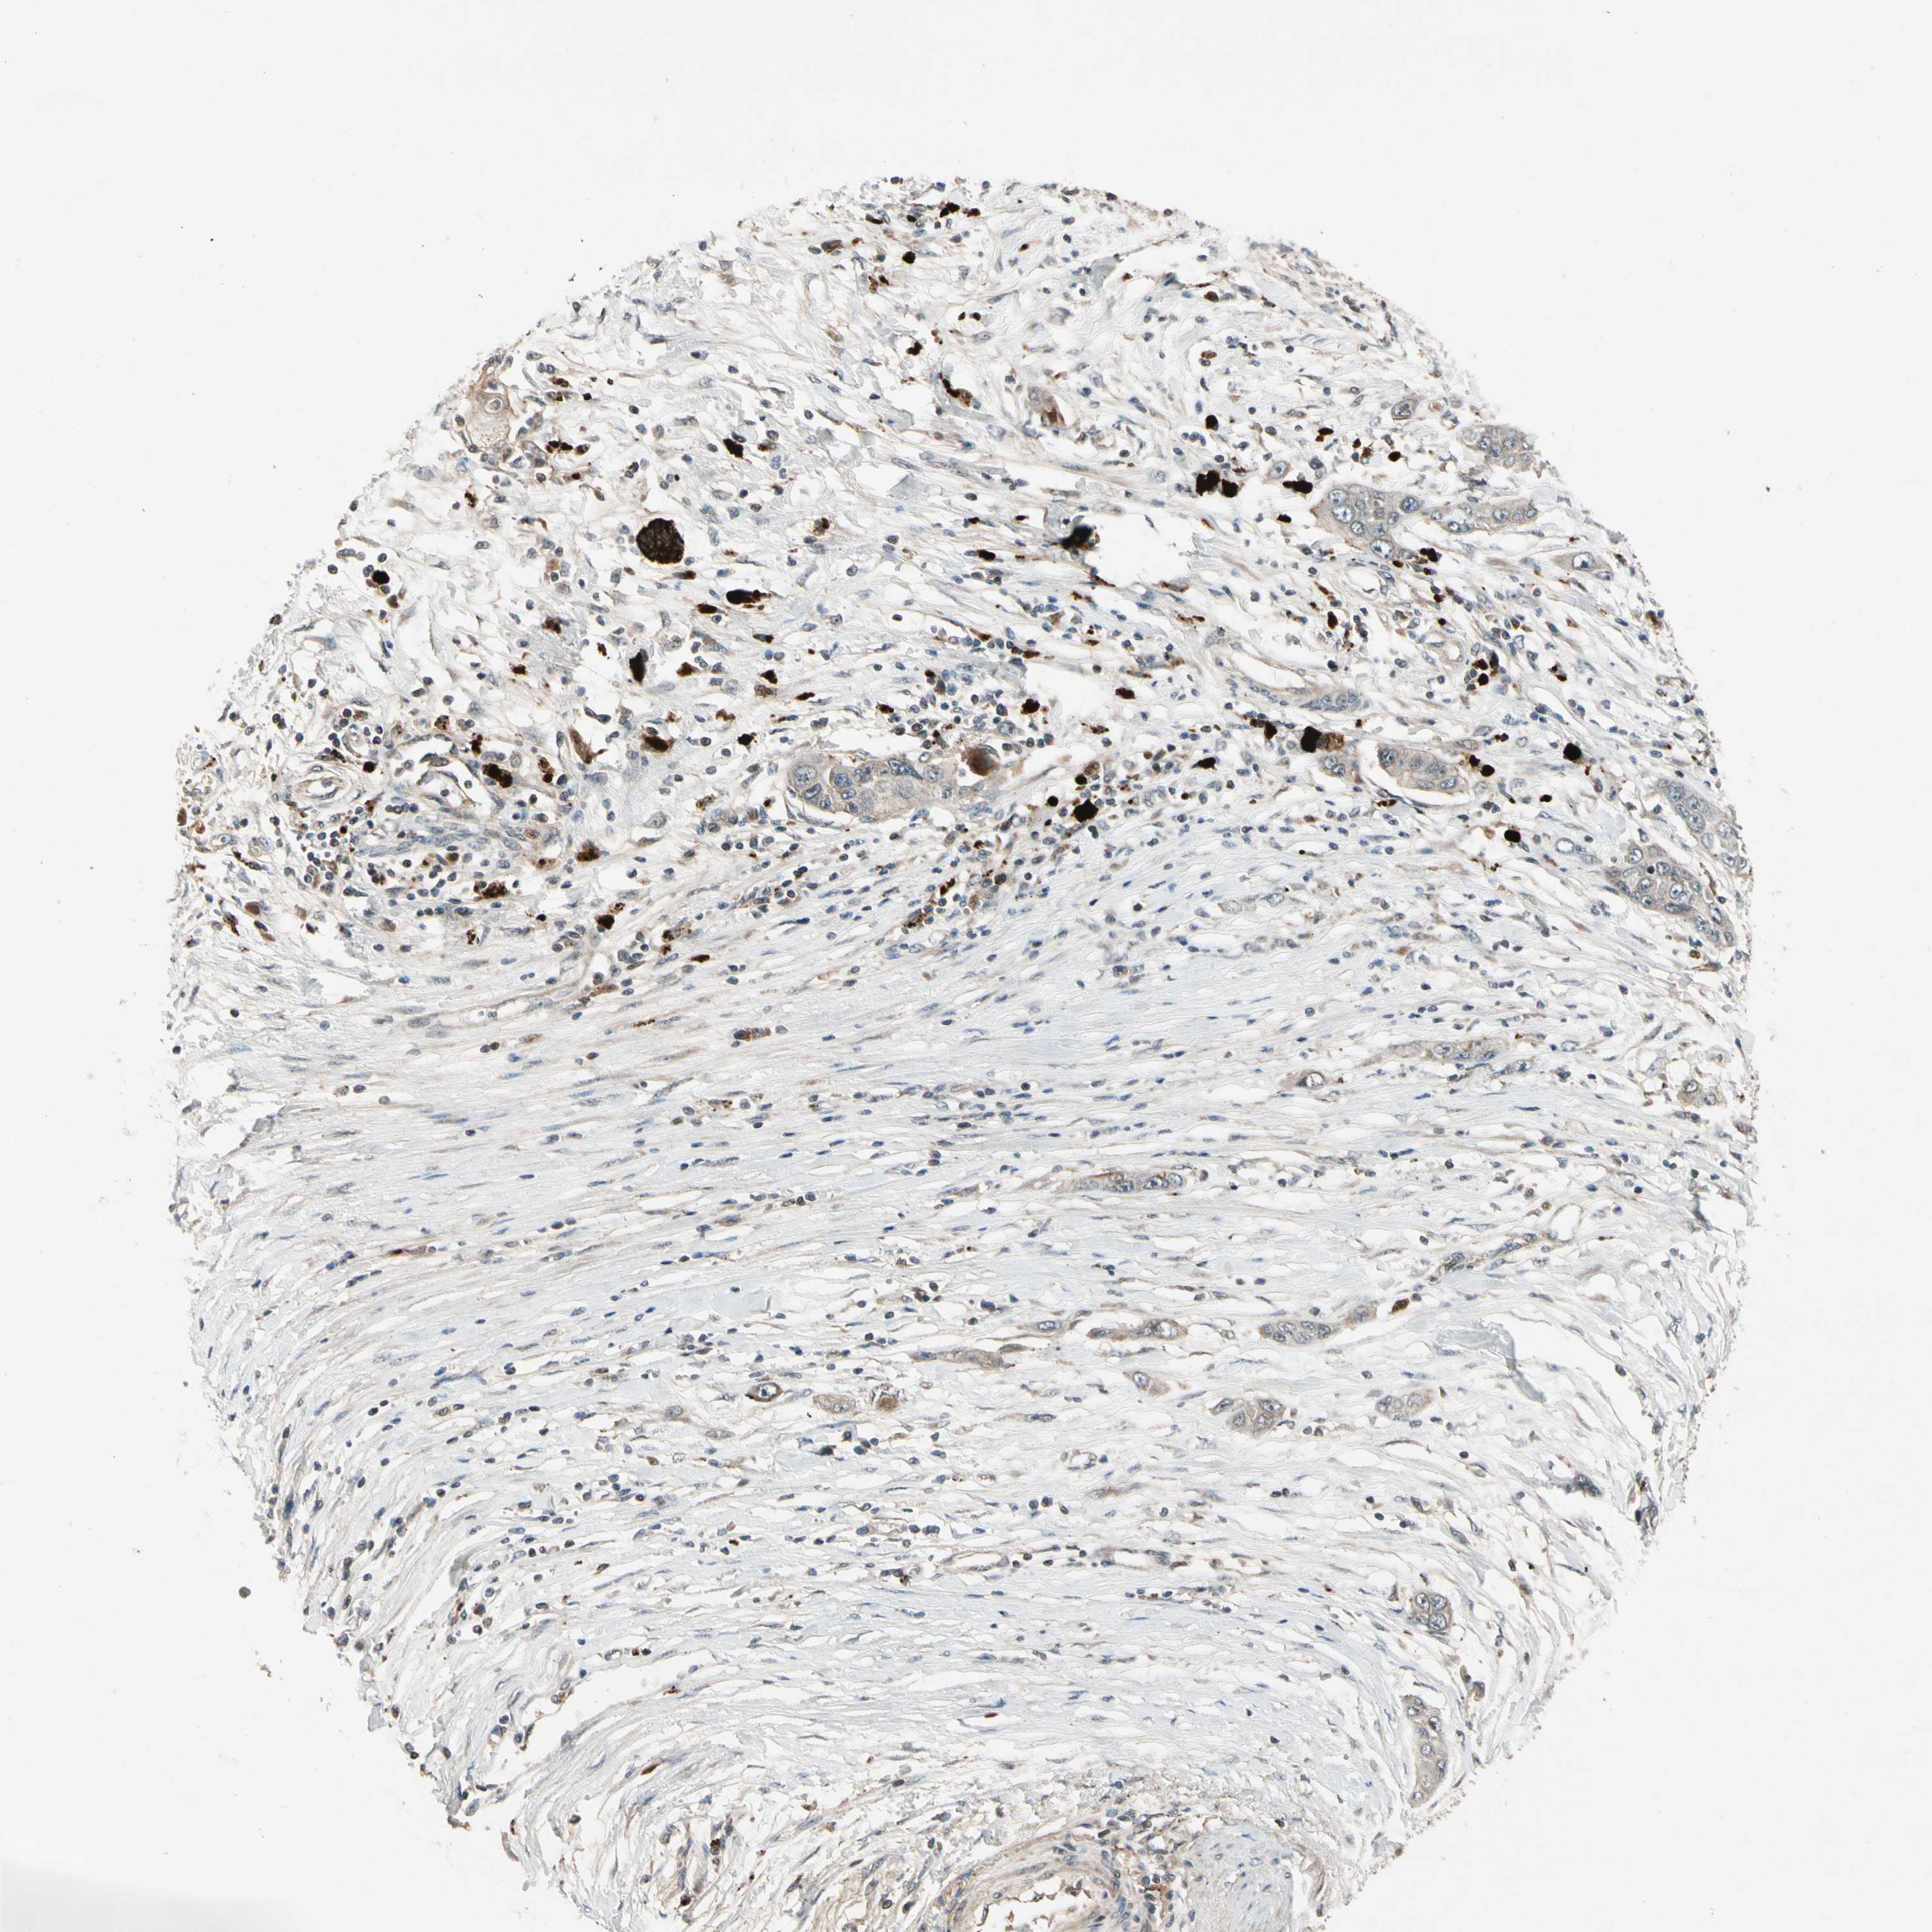

PANCREATIC CANCER - Protein expressioni

A mouse-over function shows sample information and annotation data. Click on an image to view it in a full screen mode. Samples can be filtered based on level of antibody staining by selecting one or several of the following categories: high, medium, low and not detected. The assay and annotation is described here.

Note that samples used for immunohistochemistry by the Human Protein Atlas do not correspond to samples in the TCGA dataset.

Antibody stainingi

Antibody staining in the annotated cell types in the current human tissue is reported as not detected, low, medium, or high, based on conventional immunohistochemistry profiling in selected tissues. This score is based on the combination of the staining intensity and fraction of stained cells.

Each image is clickable and will lead to virtual microscopy that enables deeper exploration of all samples and also displays staining intensity scores, fraction scores and subcellular localization as well as patient and tissue information for each sample.

Antibody HPA007982

Antibody HPA011933

Staining

High

Medium

Low

Not detected

Intensity

Strong

Moderate

Weak

Negative

Quantity

>75%

75%-25%

<25%

None

Location

Nuclear

Cytoplasmic/membranous

Cytoplasmic/membranous,nuclear

Adenocarcinoma, NOS

Adenocarcinoma, metastatic, NOS